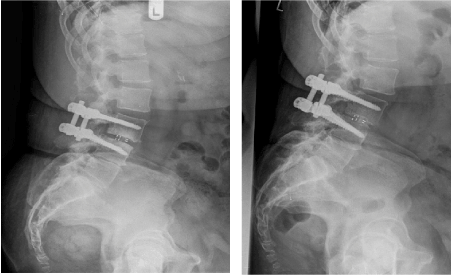

Figure 1: Left post-operative after surgery; right at least one year after surgery